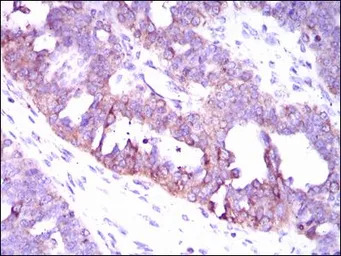

IHC-P analysis of ovarian cancer tissue using GTX60667 CaMKIV antibody [8C5B8].